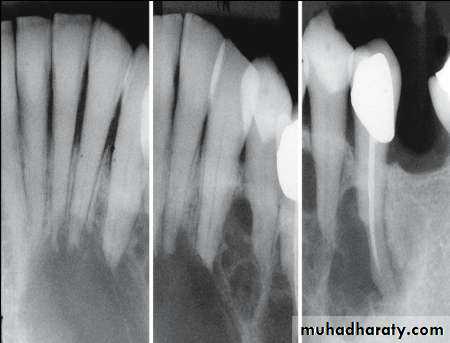

• Cementoblastoma

• Radiography:• Typically appears as radio opaque rounded mass with thin radiolucent margin.

• Attached to the root.

• Resorption of the related root is common.